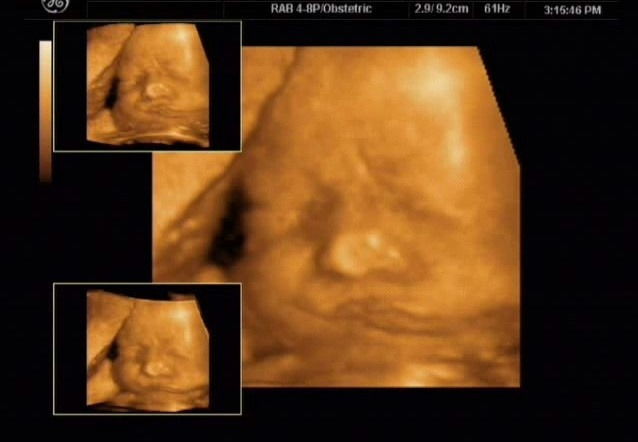

경태 엄마가 가지고 온 입체 초음파 사진 두 장은 태아가 엄마의 마음을 즉각적으로 감지한다는 것을 증명해 준다. ( 경태는 아기의 태명이다. )

하루는 경태 엄마가 병원으로 산전 진찰을 갔다. 긴 시간이 지나도록 호출을 하지 않아 간호사들에게 이유를 물었다. 병원의 실수로 예약자 명단에 빠진 것을 알게 되었다. 해결을 하는 과정에서 경태 엄마는 화가 났다. 병원 관계자들의 사과로 문제는 해결되었으니 이미 시간은 많이 지나간 후였다. 입체 초음파실로에 들어가 침대에 몸을 뉘이고 심호흡을 했지만 계속 속이 상했다. 화면을 보자 경태가 보였다. 초음파를 보던 선생님이 놀라며 말했다. “아기 좀 보세요. 얼른 화 푸셔야겠네요. 경태도 엄마처럼 찡그리고 있잖아요.”화면 안에는 미간을 찡그리고 갈 지자 모양을 하고 있는 입이 보였다. 누가 봐도 화가 난 얼굴이다. 소름이 돋았다. 나의 마음과 경태의 마음이 같았구나.

순간 진정으로 미안한 마음이 들었다. 미안하다는 말을 계속 했다. 5분 가량 지나자 화면 속 경태의 얼굴이 펴졌다. 내려간 입 꼬리와 미간의 주름이 없어진 것이다. 입가에는 옅은 미소마저 보이는 것이 아닌가! 남은 임신기간 동안에는 되도록이면 화를 내지 않겠다고 다짐을 했다.

경태는 잘 태어나 벌써 중학생이 되었다. 지금까지 그사진은 보물처럼 간직하고 있다. 어디를 가던 출산교육 자료로는 최고이기 때문이다. 세상의 어떤 말보다 경태 사진 두 장이면 태교는 끝이 난다.